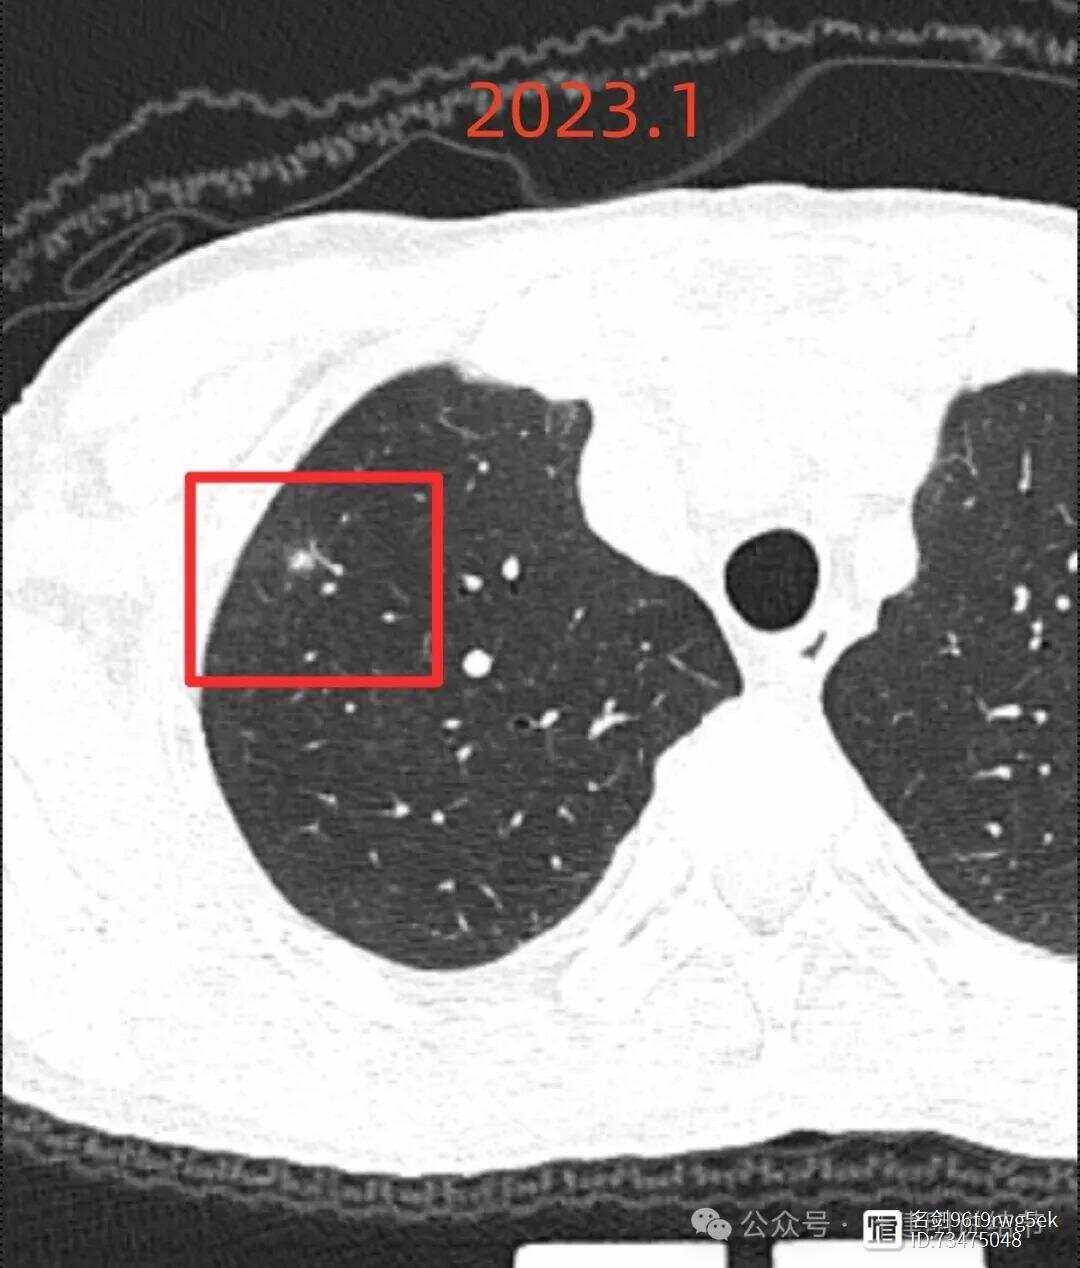

肺部CT有阴影可能涉及多种疾病,具体如下感染性疾病肺炎由细菌病毒支原体等感染引起细菌性肺炎中,肺炎链球菌是常见病原体,CT表现为肺部片状或斑片状阴影,伴有发热咳嗽咳痰等症状,各年龄段都可能患病,儿童因免疫系统发育不完善更易感染,有呼吸道感染接触史等生活方式的人群患病风险相对较。